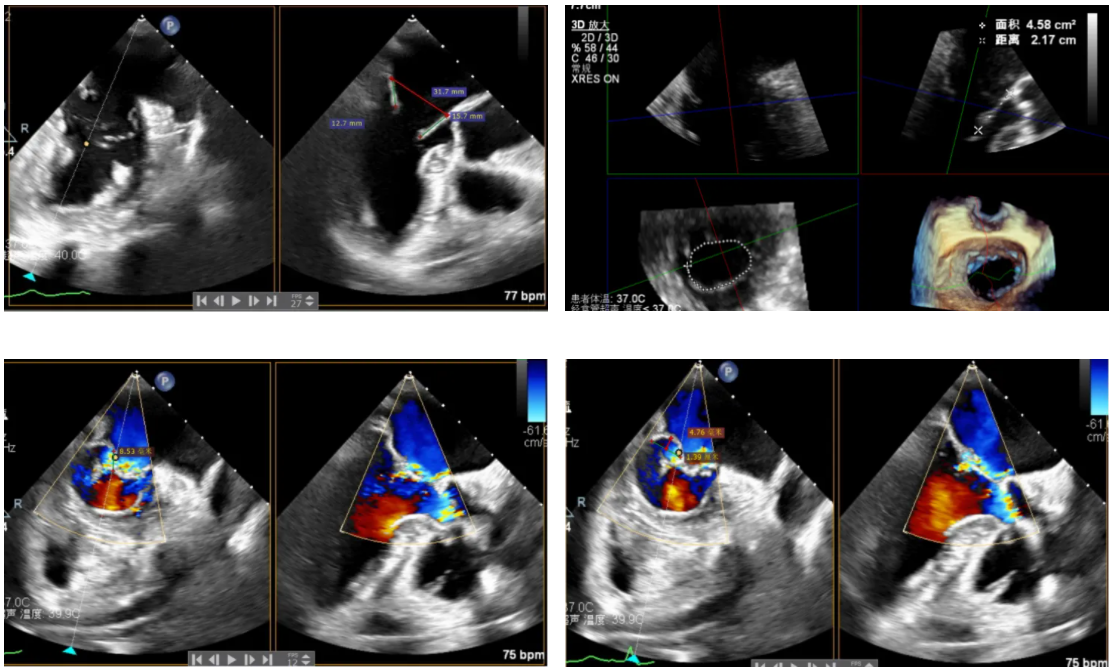

全麻后,二尖瓣夹合器系统在心前区的肋间切开3-4CM小切口,暴露心脏的心尖位置,送系统送入左心房,顺利到达病变二尖瓣区域。在经食道超声辅助下,术者通过反复评估二尖瓣反流位置、抓捕位置、反流程度,首先在2偏3区位置处于二尖瓣闭合线垂直进行巧妙夹合。在2区靠近3区位置处植入了1枚ValveClamp®MVC-IIf夹,最终评估评估反流降至轻度,平均跨瓣压差降至2mmHg,手术取得圆满成功。

术中超声(关键步骤)

最终在A3P2位置夹合,前叶夹合量10mm,后叶夹合量8mm,剩余瓣口面积3.45cm²,平均跨瓣压差2mmHg,反流基本消除。